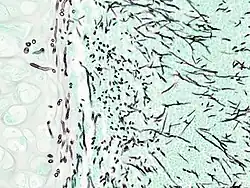

Aspergiloza (łac. aspergillosis) jest zakażeniem lub reakcją alergiczną wywoływaną przez grzyby z rodzaju Aspergillus (kropidlak). Postacie aspergilozy o największym znaczeniu to poważne infekcje płucne u pacjentów z obniżoną odpornością, takich jak chorzy na AIDS, leczeni chemioterapią lub antybiotykami przez dłuższy czas. W alergiach Aspergillus odgrywa mniejszą rolę.

Aspergillozę najczęściej wywołuje Aspergillus fumigatus, w ostatnich latach także Aspergillus flavus, Aspergillus niger, Aspergillus glaucus i Aspergillus nidulans[1]. Postać inwazyjna może zająć oko (powodując ślepotę), a także każdy inny narząd ciała, ale zwłaszcza serce, płuca, mózg i nerki. Trzecia postać występuje prawie wyłącznie u ludzi z obniżoną odpornością z powodu nowotworu złośliwego, AIDS, terapii immunosupresyjnej (u biorców przeszczepów), przyjmowania wysokich dawek sterydów, chemioterapii lub innych chorób, w których występuje obniżona zawartość białych krwinek.